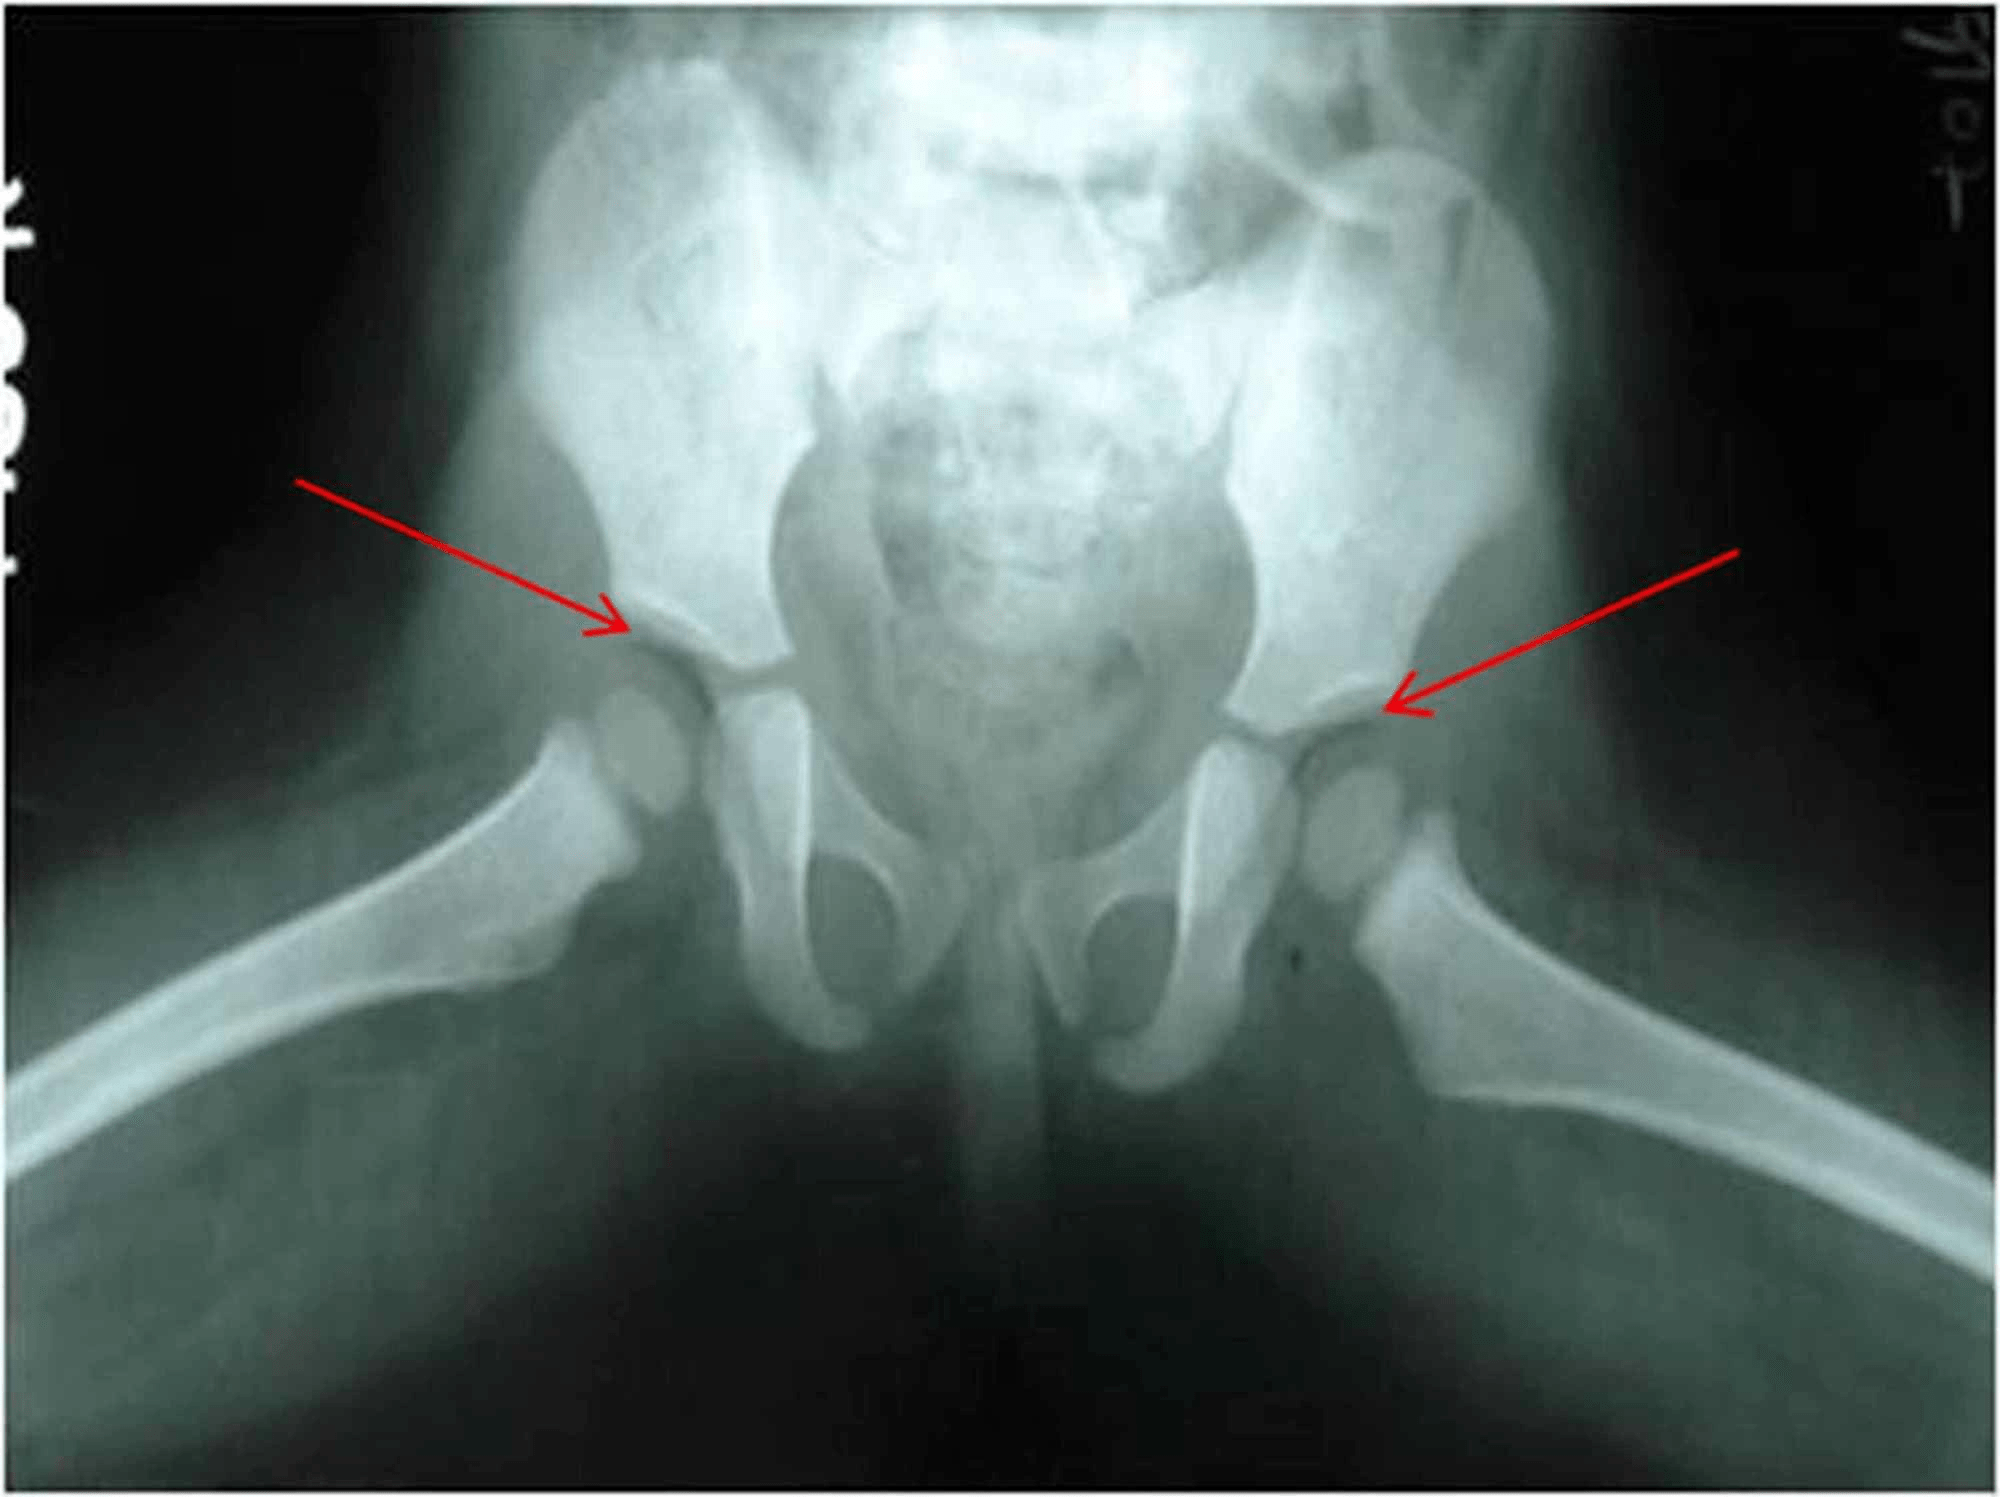

Figure 1 from Vacuum Phenomenon of the Sacroiliac Joint Correlation Air Vacuum Phenomenon It has been described commonly in the spine and. ‘vacuum phenomenon’ or ‘pneumoarthrosis’ term is used when there is air within a joint space. Most cases of intravertebral vacuum phenomena are of a benign nature. Appearance and signal characteristics are those of air that will be seen as radiolucency on a radiograph and as an air. While vacuum disc phenomenon. Air Vacuum Phenomenon.